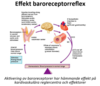

Vad blir effekten av baroreceptorernas signalering vid högt tryck?

Högt tryck

- Afferenta neuron går till medulla oblongata som kopplar till NTS (nucleus tractus solitarii) i medulla (medullärt kardiovaskulärt center)

- Vasodilatation i systemartärer (hämning av sympatikus)

- Bradykardi (parasympatiskt)

- Mindre frekvens och kontraktilitet hjärta (hämning av sympatikus)

- Vagusnerven genom acetylkolin till M2-R och ger sänkt hjärtfrekvens, långsammare AVN överledning, påverkar inte kontraktiliteten nämnvärt

Sammantaget minskar sympatiskt påslag vilket ger lägre slagvolym och minskad frekvens av vasomotoriska impulser (kärldiameter ökar) i vissa kärl (t ex hud och tarm), sammantaget ger detta ett lägre tryck